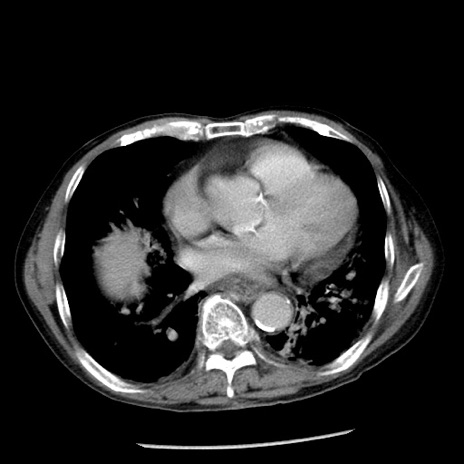

症例26(横断像)

【症例】80歳代男性

【主訴】嘔吐

【現病歴】昨晩2回嘔吐あり、今朝になっても嘔吐あり。来院。

【既往歴】胃潰瘍

【身体所見】意識清明、BT 37.6℃、BP 166/95mmHg、HR 100bpm、SpO2 97%、腹部:平坦・軟、腸蠕動音聴取良好、圧痛なし。

【データ】WBC 21900、CRP 1.46